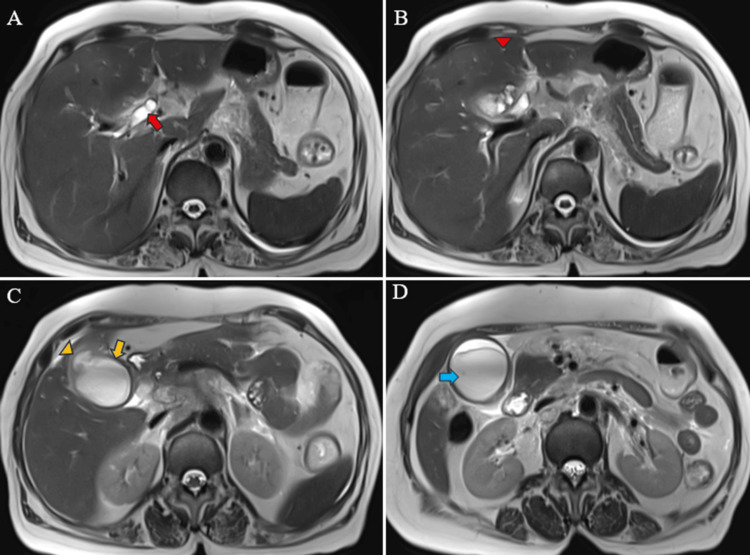

Magnetic resonance (MR) abdomen imaging with MR cholangiopancreatography (MRCP) revealed an overdistended gallbladder with circumferential wall thickening measuring 4 mm. Bile appeared hypointense on T2-weighted imaging (T2WI), indicative of sludge or thick material, with diffusion restriction on diffusion-weighted imaging (DWI) and low apparent diffusion coefficient (ADC) values. A 7 mm defect was noted in the body region, with T2 hyperintense pericholecystic fluid collection demonstrating diffusion restriction adjacent to the body. Mild dilatation of the IHBR was observed in both the right and left lobes. The CBD measured 8 mm in diameter, with narrowing of the mid-CBD due to circumferential wall thickening measuring 4 mm. The remainder of the CBD appeared normal in caliber (Figures 9–10).

Multiple enlarged lymph nodes were noted at various locations, including the porta hepatis, peripancreatic region adjacent to the pancreatic head, celiac region, aorto-caval region, pre-aortic, left para-aortic region, and retrocaval region (Figure 11). These lymph nodes exhibited T1WI hypointensity and T2WI heterogeneous hyperintensity, with central necrotic areas of variable sizes. Some lymph nodes demonstrated diffusion restriction on DWI and appeared coalescent. The pancreas appeared normal. Visualized lower lobes of both lungs exhibited well-defined T2WI hyperintense lesions ranging in size from 2 to 15 mm, with peripheral and subpleural distribution.

These findings were suggestive of a stricture in the mid-CBD, likely neoplastic (cholangiocarcinoma), resulting in proximal biliary obstructive dilatation. Additionally, the gallbladder exhibited changes consistent with empyema and contained perforation. Multiple metastatic lymph nodes were observed in the retroperitoneum and porta hepatis, along with multiple lung metastases.